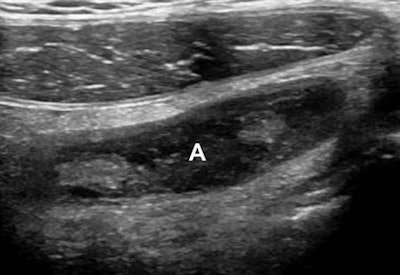

- Loss of the submucosal layer: Defined as either focal or global lack of visualization of the normally echogenic layer, confirmed in both the long- and short-axis views of the appendix

The researchers compared those results with the presence or absence of complicated versus uncomplicated appendicitis as determined histopathologically. Of the 119 patients, 32 (26.9%) had complicated appendicitis; 21 had gangrenous appendicitis and perforation, while 11 had gangrenous appendicitis without perforation.

After performing multivariate regression analysis, the researchers found that the loss of the submucosal layer was the only independent, statistically significant (p < 0.001) sonographic indicator of complicated appendicitis, yielding 100% sensitivity (95% confidence interval: 89.1%-100%) and 92% specificity (95% confidence interval: 84.1%-96.7%).